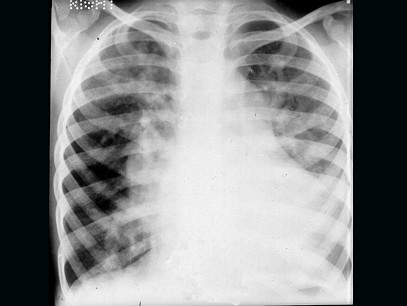

患儿男,4岁,生后反复发生呼吸道感染,发育差,活动后气促,无发绀。听诊胸骨左缘第3肋间可闻及Ⅲ级粗糙的全收缩期杂音,肺动脉第2音显著亢进,X线示如图:肺野明显充血。该患儿最易并发下列哪种疾病 ( ) EK-04859.jpg